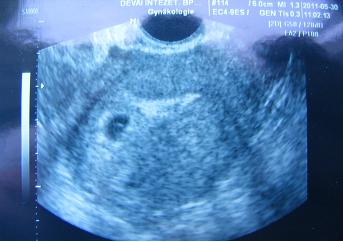

Puszik, pocaksimi!